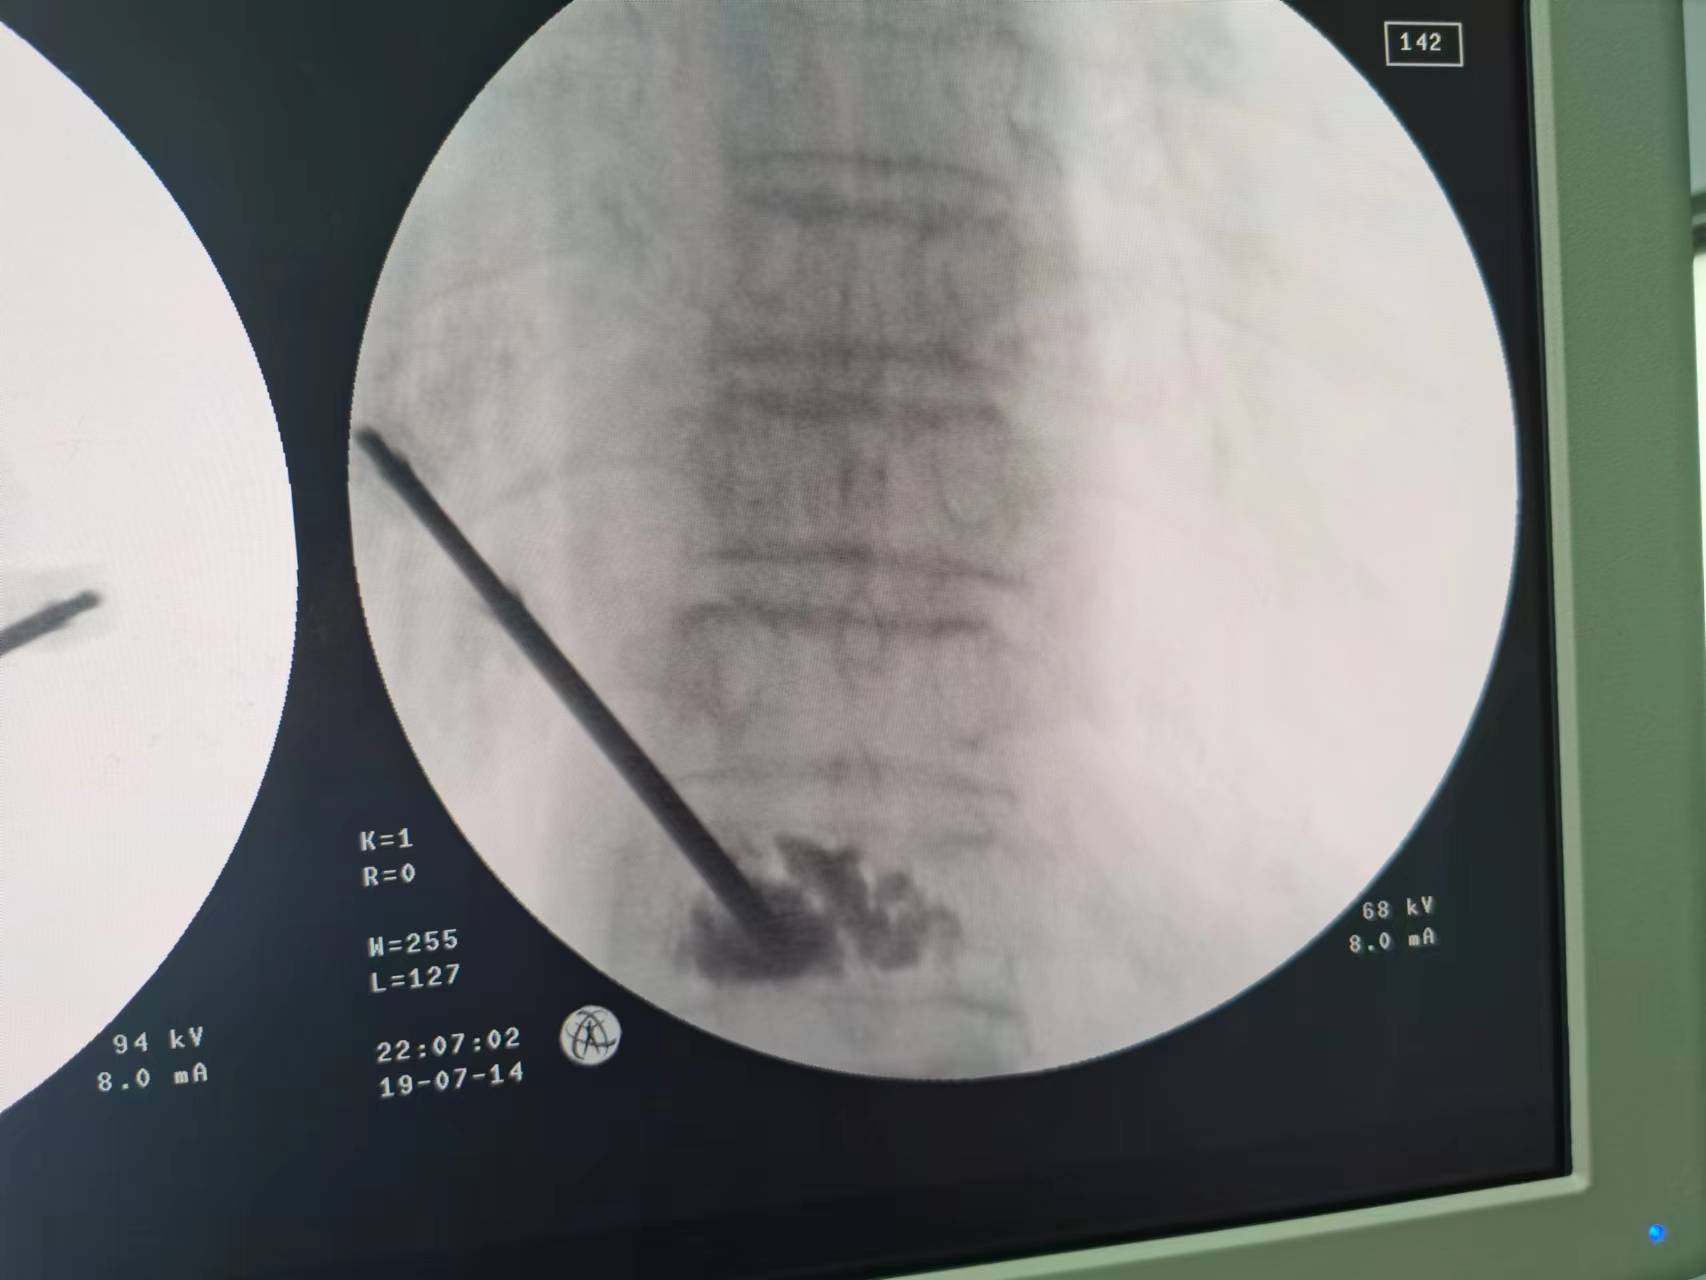

术前

骨质疏松胸腰椎压缩性骨折多发生在老年人,均在骨质疏松基础上发生,有时并没有明显外伤病史,因骨质疏松甚至咳嗽或打喷嚏都可能引起骨折。骨折后因疼痛较剧烈,翻身都较困难,病人较痛苦,严重影响患者生活质量,目前治疗上均采用微创手术“经皮穿刺椎体成形术”,术后马上减轻疼痛9成以上,手术效果非常好,第二天就能下地。

李伯随即转入骨科治疗,张勇华副院长、骨科主任带领的骨科团队经讨论,详细制定手术方案并征得家属同意,决定尽快为李伯进行“经皮穿刺椎体成形术”,手术由李竖飞、林勇医生完成,手术顺利,术后2小时腰背部疼痛明显缓解,第二天李伯便可戴腰围下地行走,很快顺利出院,精神状态及身体各方面恢复良好。00:

术后